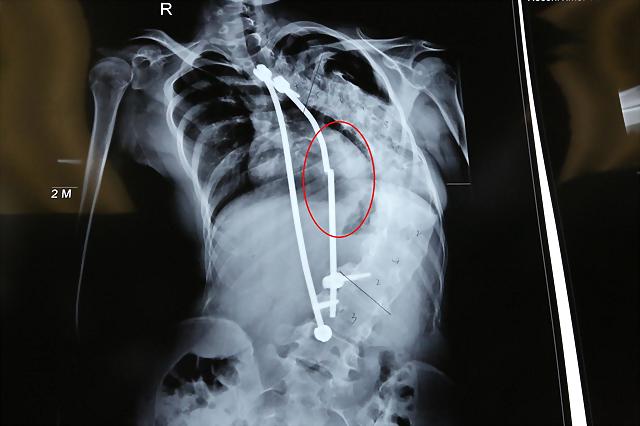

12月3日,河南南阳一医院里,由于无钱手术的何永格躺在病床上两眼淌泪。5年前,她被确诊为先天性脊柱侧弯,后背上就像长着个大大的包。3年前,一群爱心人士出钱为她做了手术,在身体里安装了矫正脊柱的生长棒。按照医嘱第二年要取掉做手术的,由于家里没钱3年时间迟迟没有手术。近一年里,何永格身高长得很快,脊柱骨变形得越发厉害,像一张拉满的弓。几天前,正在上课的她一弯腰,生长棒突然崩断了,被紧急送往医院。

2014年,身边的爱心人士得知这一家的情况后,纷纷慷慨解囊为何永格筹齐了手术费。经过手术,在她体内加了矫正脊柱的生长棒。由于她正是发育期,身高长得快,按照医嘱第二年就需要取掉做脊柱侧弯手术。可一贫如洗的家里,只有妈妈一人挣钱养家。3年过去了,家里也没攒够给孩子第二次的手术费。

几天前,何永格上课期间,弯腰捡了一下掉在地上的笔。随着一阵剧烈疼痛袭来,她被老师和同学紧急送往了医院。经过检查,身体里面的生长棒一根发生了崩断,下面固定的螺丝也脱落了一颗。